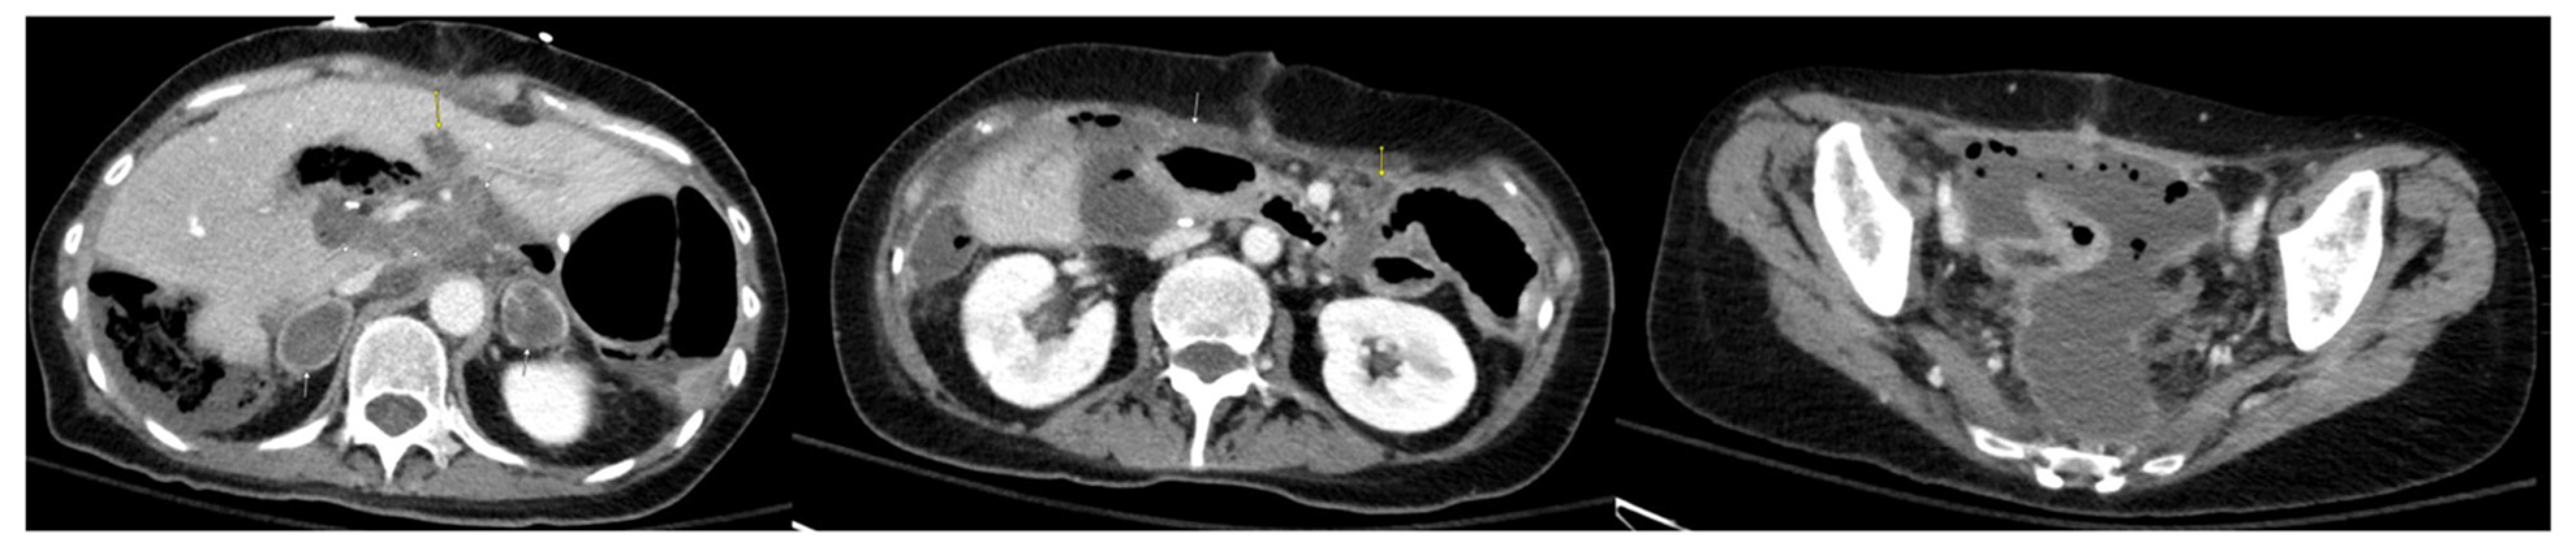

2. Case